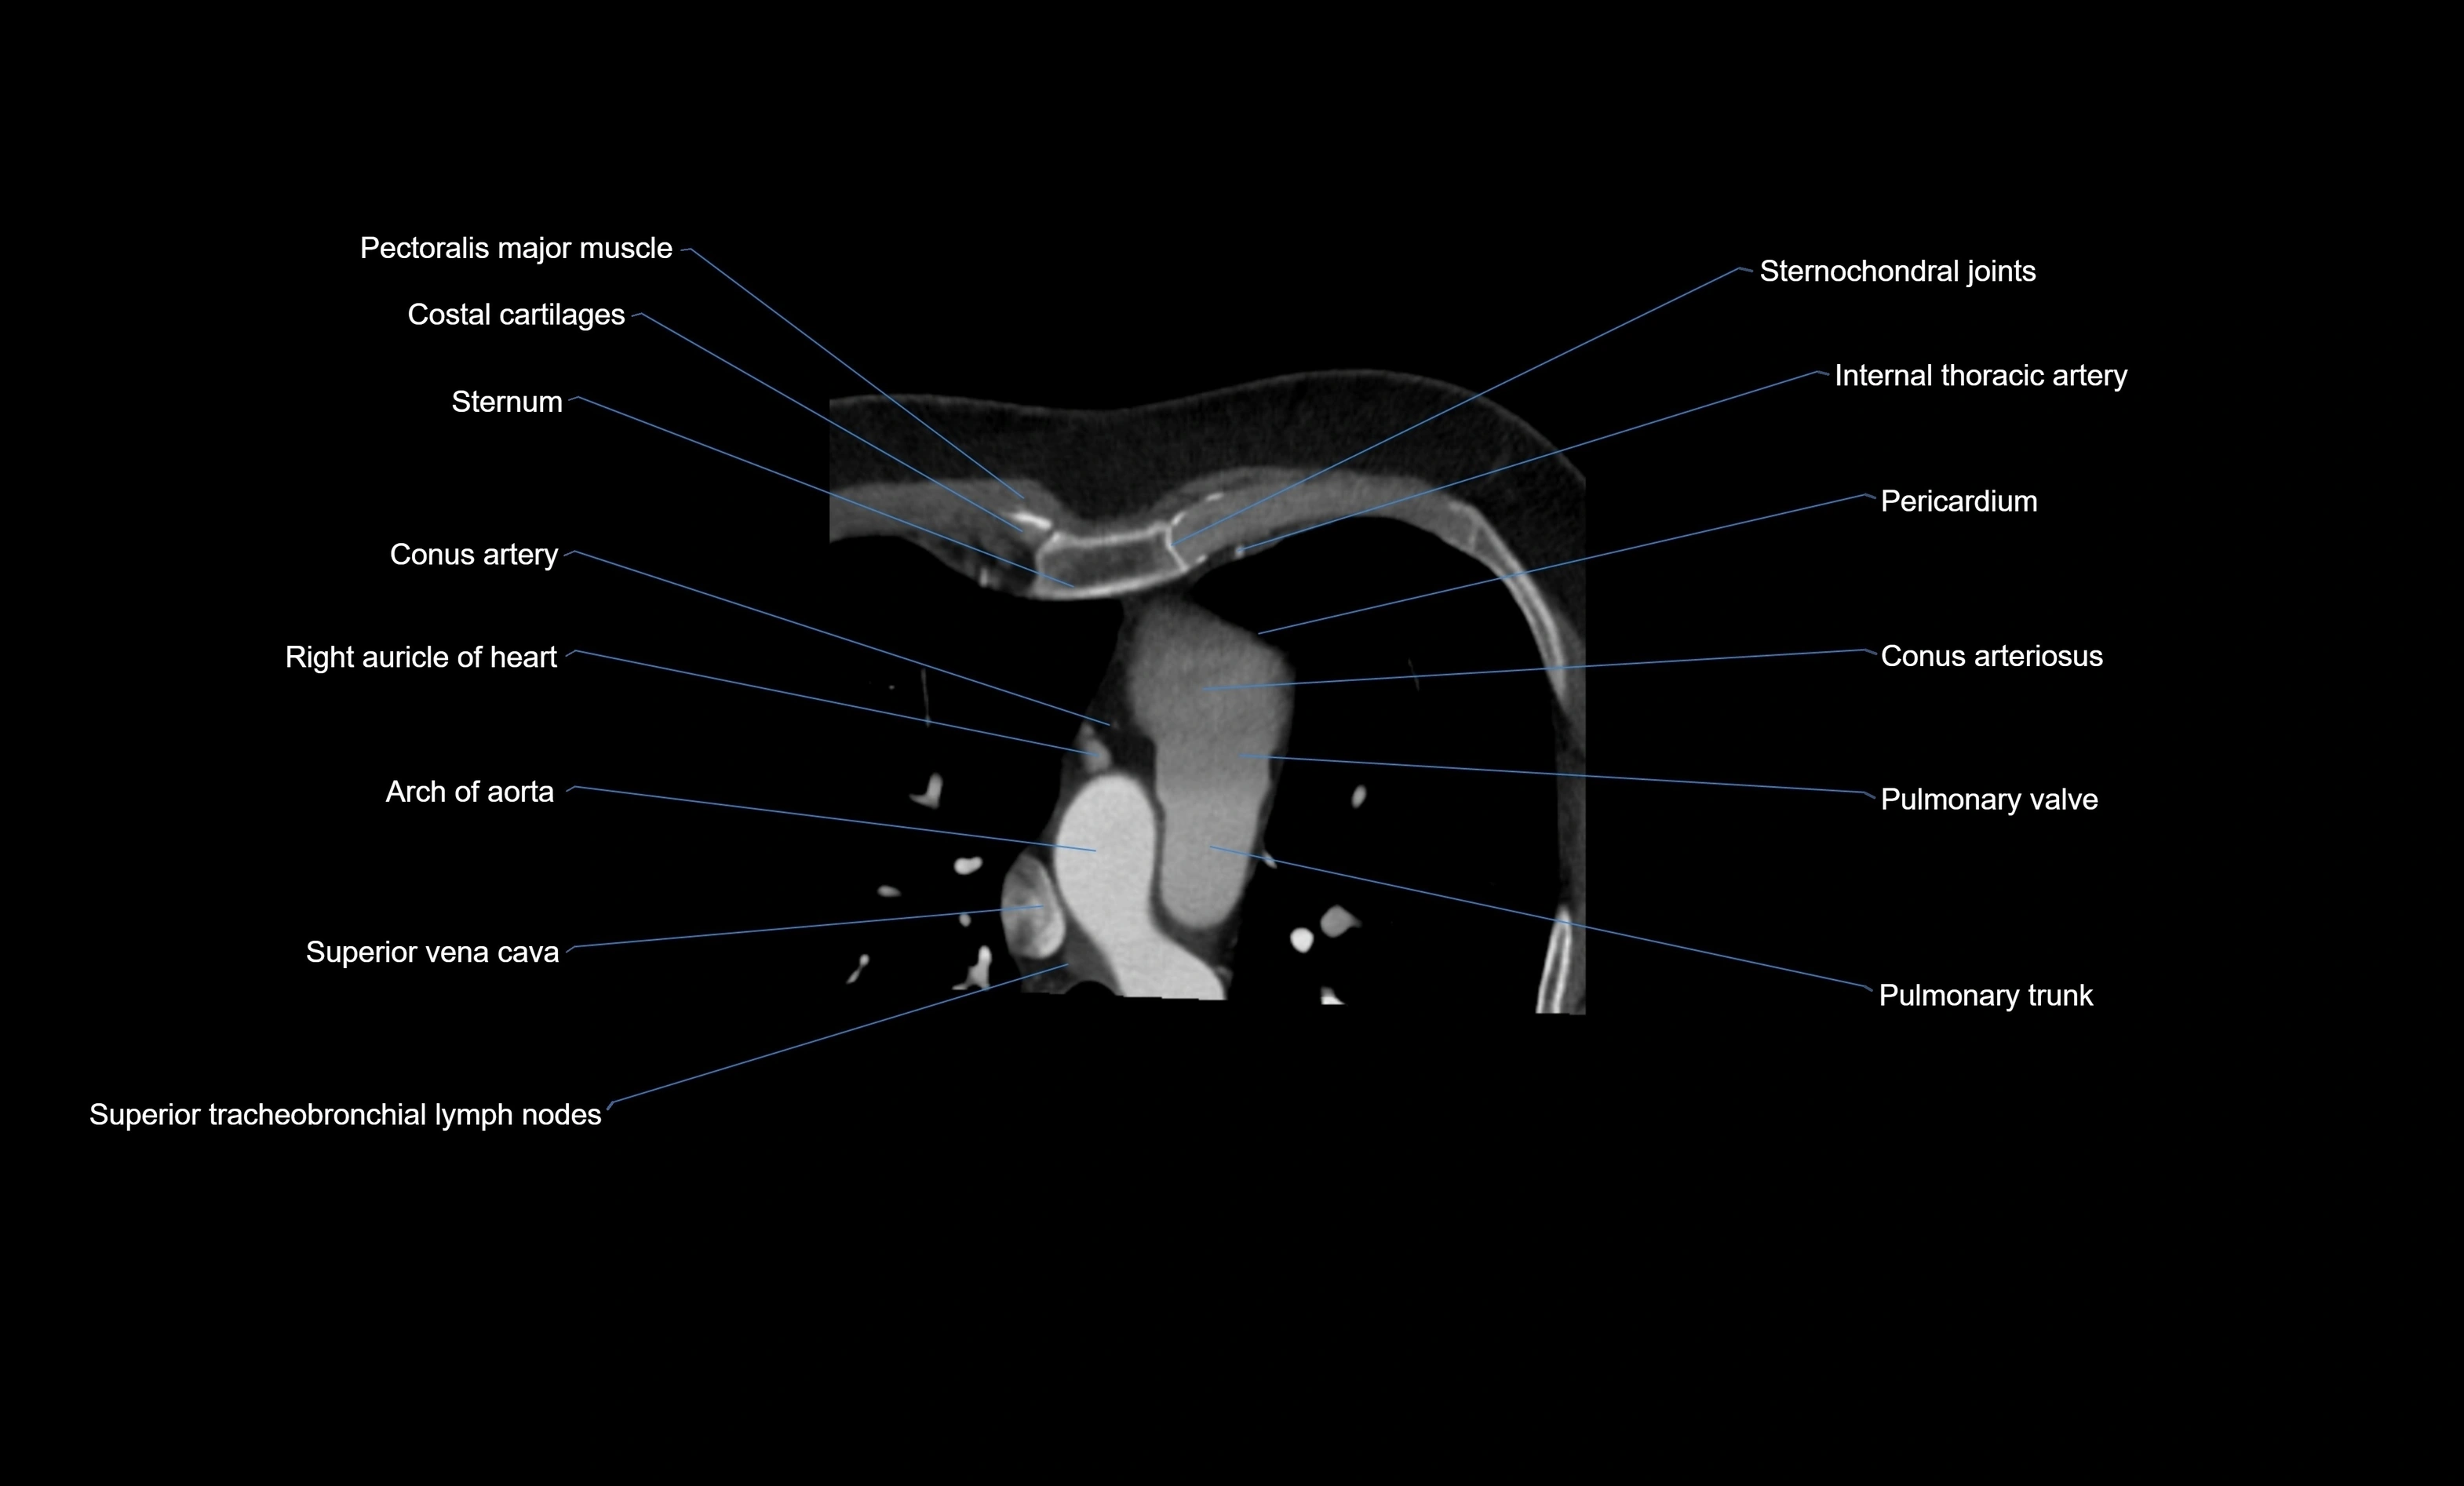

CT images